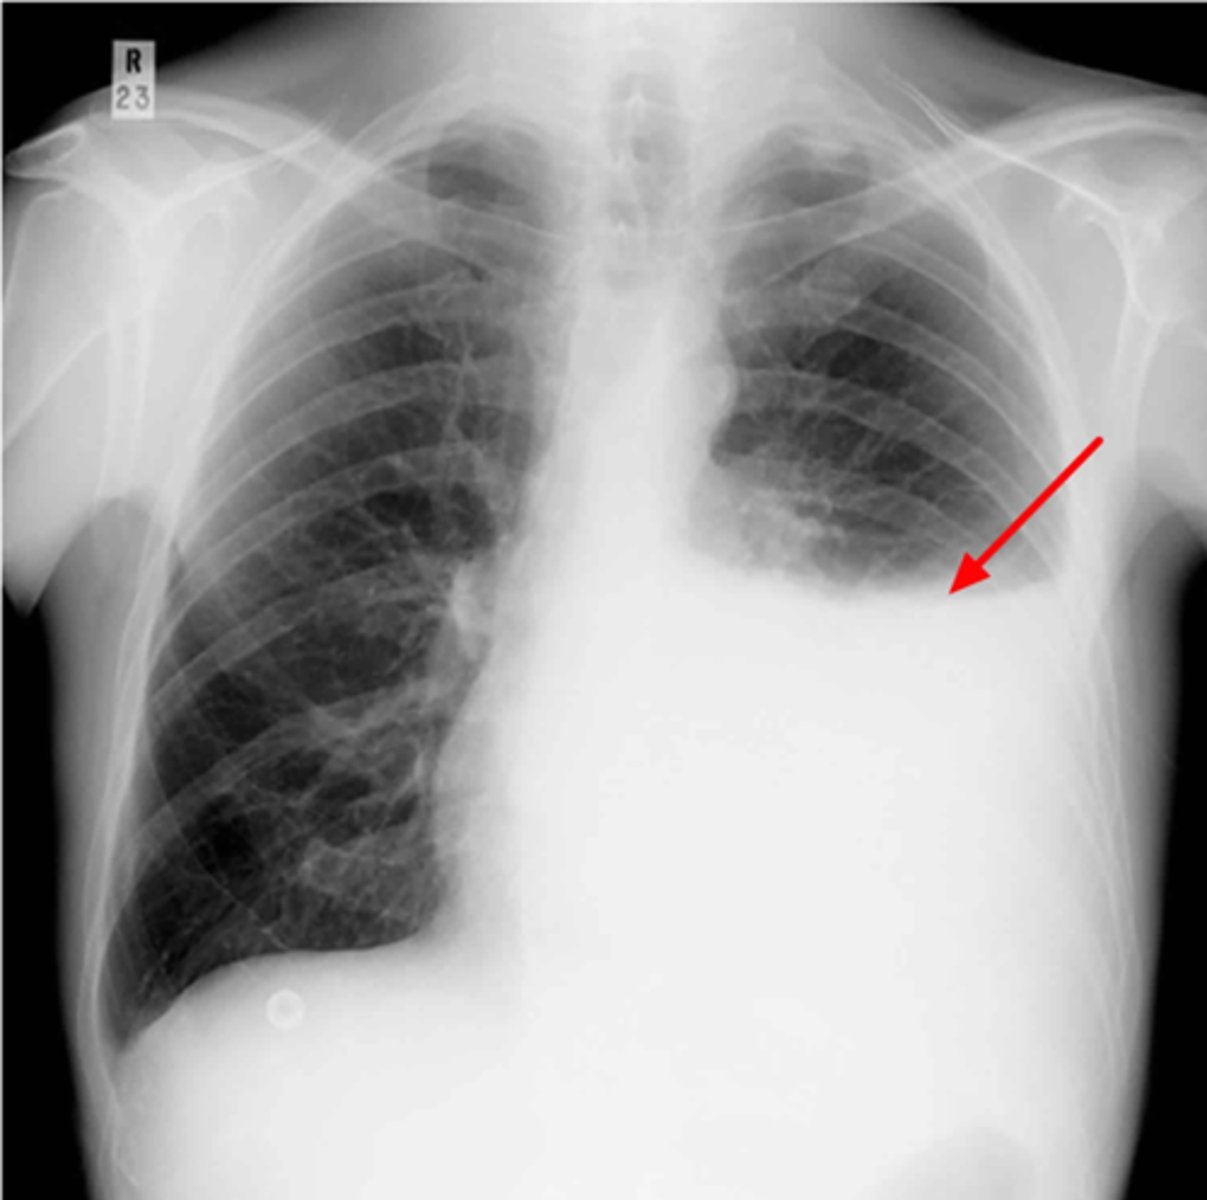

Where is the abnormality located in the chest?

Atelectasis

What is the red arrow indicating?

Effusion

What is the likely interpretation?